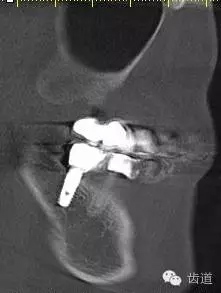

5、右下頜側(cè)面觀

7、45,46,47CBCT